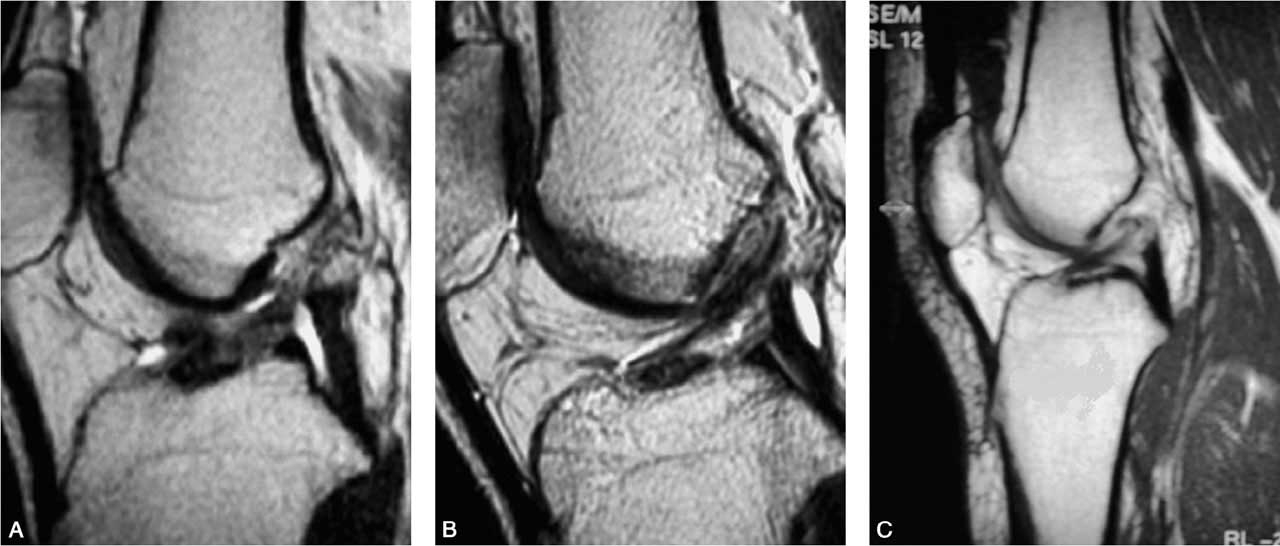

前交叉韧带慢性损伤的磁共振成像

A.前交叉韧带信号消失;B.前交叉韧带信号不规则;C.前交叉韧带信号移位

前交叉韧带慢性损伤的磁共振影像表现为三种情况:信号消失、信号不规则和信号移位。前交叉韧带损伤后韧带组织被完全吸收,磁共振成像上则表现为信号消失。

前交叉韧带损伤后有残存的少量纤维和瘢痕组织被滑膜包绕,即为信号不规则,它包括信号密度不均、粗细不均、迂曲无张力等。信号移位是指前交叉韧带自股骨止点撕脱后瘢痕粘连在后交叉韧带上。